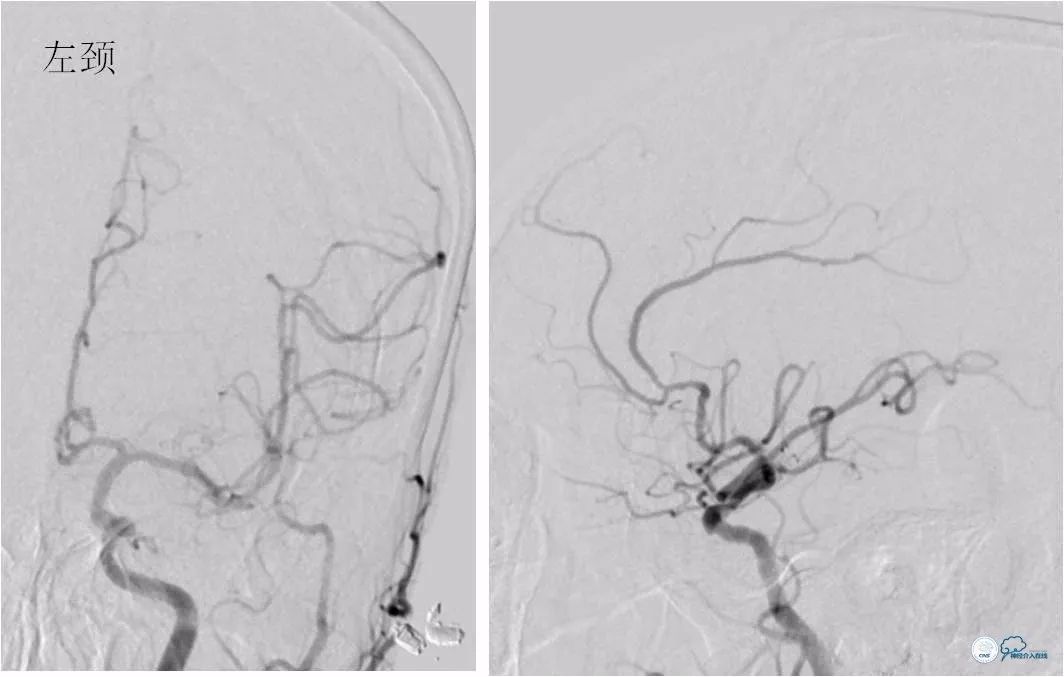

DSA:左椎动脉优势,左椎动脉V1段重度狭窄,右椎动脉V1段中度狭窄,双椎动脉V4-基底动脉下段重度狭窄,狭窄率约为85%,狭窄段有AICA发出,双侧后交通动脉未开放(图6-9)。

图6

图7

图8

图9